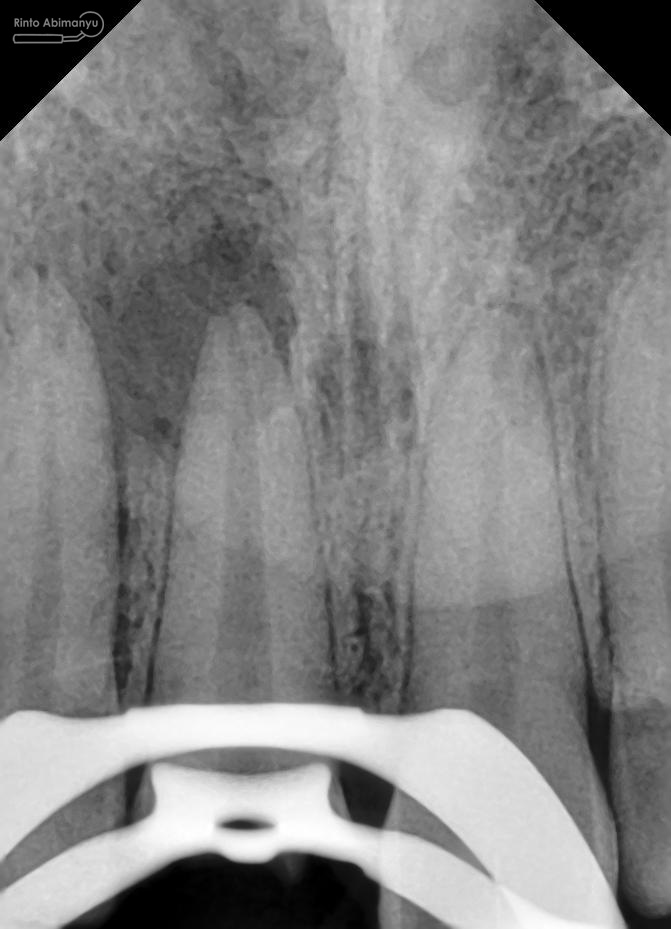

Kemudian dilakukan pengepasan guttap dan difoto ronsen….

Foto radiografis trial guttap

Dari ronsen terlihat guttap sudah pas dan langsung hari itu juga saya lakukan pengisian saluran akar kemudia pasien pulang…. Pada saat selesai pengisian tidak saya lakukan ronsen lagi karena saya merencanakan ronsen evaluasi pengisiannya sekalian foto ronsen saat pengepasan guttap pada gigi 22 saja biar efektif…